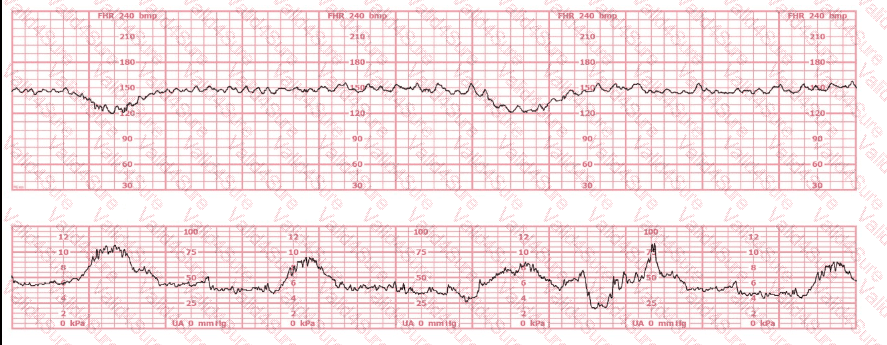

The baseline fetal heart rate in this tracing is:

A.

155 beats per minute

B.

Indeterminate

C.

Tachycardia

The fetal heart rate tracing shown represents

category I

category II

category III